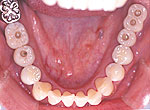

下顎臼歯のインプラント